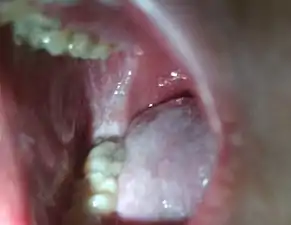

Koplik's spots seen inside the mouth are diagnostic for measles, but are temporary and therefore rarely seen.[28] Koplik spots are small white spots that are commonly seen on the inside of the cheeks opposite the molars.[27] They appear as "grains of salt on a reddish background."[30] Recognizing these spots before a person reaches their maximum infectiousness can help reduce the spread of the disease.[31]

Koplik's spots on the third pre-eruptive day

Koplik's spots on the day of measles rash

Typically, clinical diagnosis begins with the onset of fever and malaise about 10 days after exposure to the measles virus, followed by the emergence of cough, coryza, and conjunctivitis that worsen in severity over 4 days of appearing.[60] Observation of Koplik's spots is also diagnostic.[31] Other possible condition that can result in these symptoms include parvovirus, dengue fever, Kawasaki disease, and scarlet fever.[61] Laboratory confirmation is, however, strongly recommended.[62]